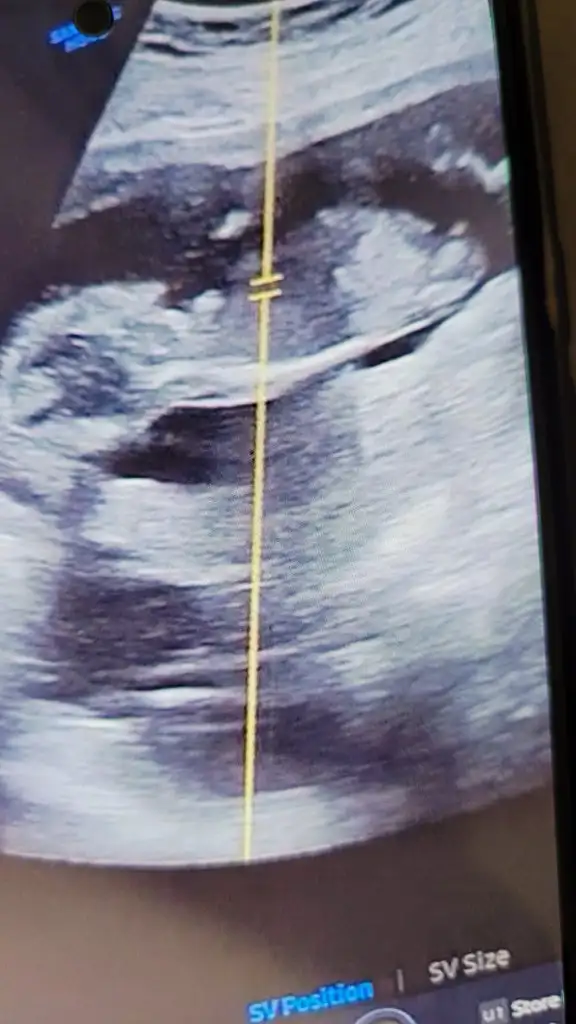

bana da yorum yapın lütfen 12+4

N Nakafile merhaba. Benim 12. haftada sırtı dönük mu anlayamadigim bir ultrason kağıdım var bu haftayı hevesle bekledim cocugum çok belirsiz bakayım siz cinsiyeti hakkinda ne diyeceksiniz acaba rica etsem yorumlar misniz :')